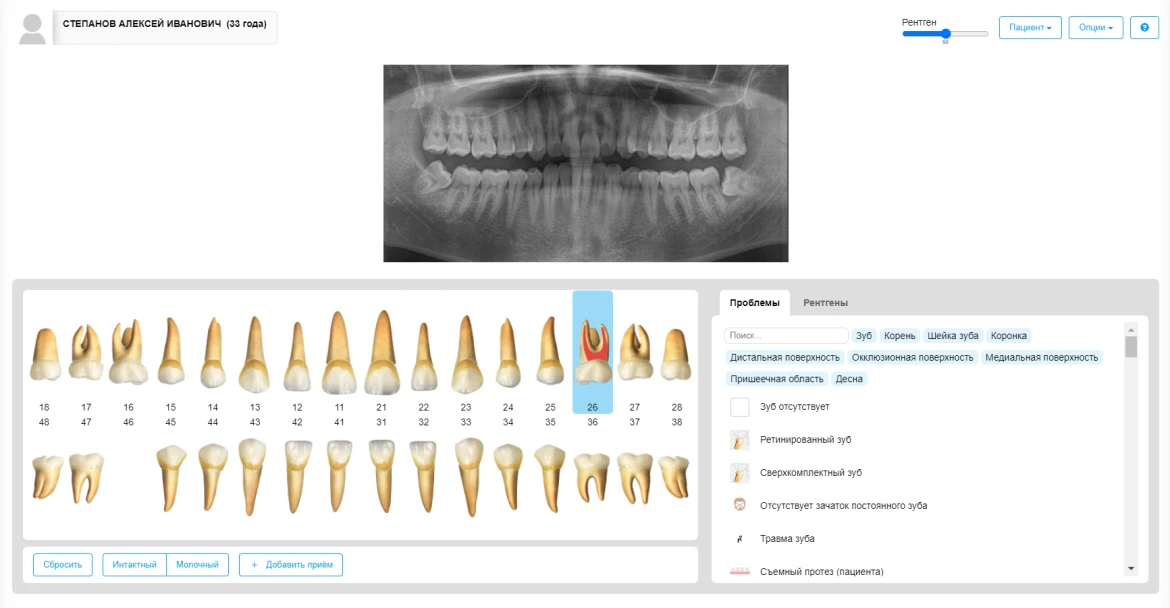

- Электронные карты пациентов: Хранение полной информации о пациентах, включая историю заболеваний, результаты анализов и планы лечения.

| Электронная медицинская карта пациента | да |

| Зубная формула (стом.карта) | да |